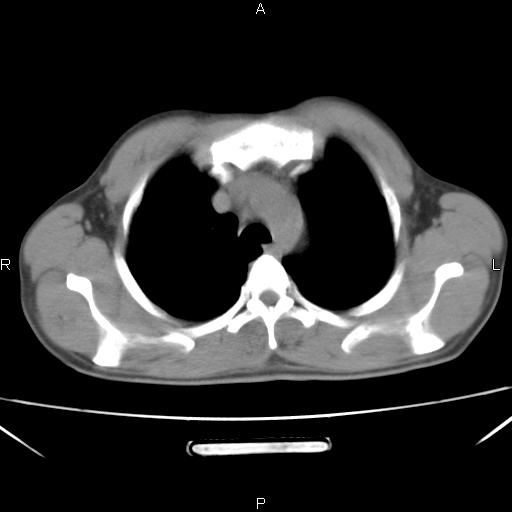

左下肺片状高密度影,境界模糊,密度不均,考虑感染性病变可能性大,建议抗炎治疗后复查。左肺门增大,不除外占位性病变,必要时支气管镜检。

考虑感染性病变可能性大,抗炎后复查,占位不排除。